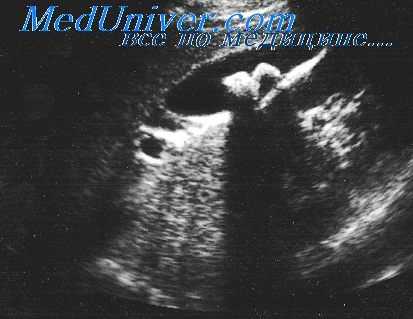

При рентгенологическом обследовании: многочисленные участки разрежения, окруженные зоной склероза.

Выявляются гомогенные секвестрообразные уплотнения со стороны поверхности головки плечевой кости с наличием четкой зоны резорбции от основной склерозированной массы головки.

Поражение эпифизарных концов трубчатой кости почти всегда сочетается с вовлечением в процесс суставных хрящей и суставных сумок

В первую очередь поражается головка и проксимальный конец диафиза бедра, затем головка и верхняя часть диафиза плеча, далее – дистальные отделы бедра, проксимальные концы большеберцовой кости, нижние концы плечевой и лучевой костей.

- Субкортикальная полоска просветления

- Разрушение суставного кортекса

- Секвестрация кортекса